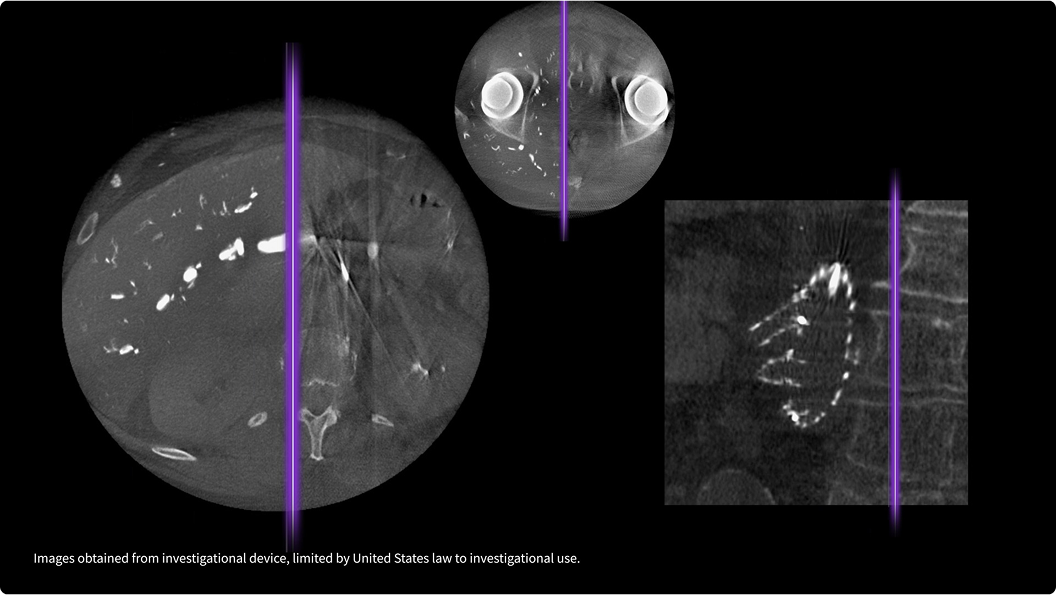

True Enhance DL is a deep learning-based processing method intended for contrast enhancement of single energy images. True Enhance DL uses a dedicated Deep Neural Network (DNN) trained to estimate monochromatic, 50 keV GSI images from single-energy X-ray. This technology brings four deep learning models that the user can choose depending on different contrast enhancement phases by clinical tasks.

TrueFidelity DL

Deep learning for a deeper understanding

TrueFidelity™ DL is our state-of-the-art image reconstruction technology that uses a DNN to generate high-definition, low-noise CT images. It produces images with exceptional sharpness, low-contrast image quality performance and your preferred noise texture, at the same dose.¹